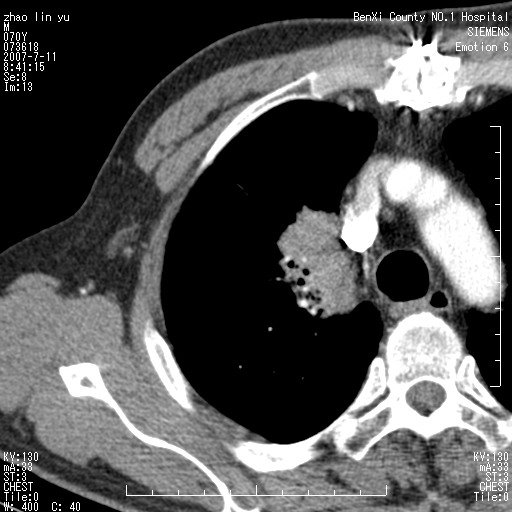

以下是引用王靖旗在2007-7-10 17:12:00的发言:[br] 男、70、咳嗽两个月,半年前换瓣手术,胸片未见异常,于昨天行x片发现右肺上野大片影,行ct扫描,这里是减薄图像,余肺正常。明天晚上会有增强扫描片,到时我会上传。[br][br] 冠状位请大家细看,应该是有意义的,[br][br] 请大家先看平扫发表意见。[br][br]

[br]冠状面[br]

以下是引用zhangzhongshou在2007-7-10 21:43:00的发言:[br]右肺上叶周围型肺癌,以孤立型细支气管肺泡癌可能性大。